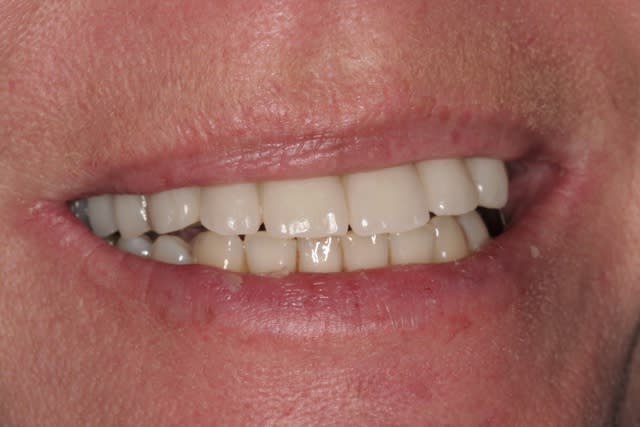

revenons en plutôt au sujet: une MCI, une patiente, et voilà la cicat à 3jours car je viens de la revoir avant ma semaine de congés (pas de pb, s'il y a quoi que ce soit elle a mon n° de portable...)

j'ai remis la photo juste post chir que vous jugiez vous même du repositionnement de la gencive qui est en train de se faire...;-)

je pense que çà va être bien joli pour le définitif...;-)